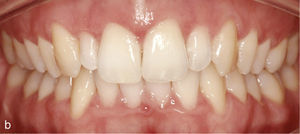

EspaciosEl cierre de espacios en el sector anterior se clasifica dentro de los movimientos dentales sencillos con el sistema Invisalign. En la vista intraoral de la figura 6a se observan sendos sectores anteriores con espacios en maxilar y mandíbula. Se realizó el cierre de los espacios y también la intrusión de los dientes 11 y 21. Con dicho fin fueron adheridos ataches rectangulares en los dientes 13, 23, 11 y 21. La imagen intraoral de la figura 6b muestra el resultado del tratamiento después de cerrar los espacios y de reducir la sobremordida vertical.

Vista intraoral de los dientes anteriores separados entre sí y de los ataches en los dientes 13, 11, 21 y 23 para el cierre de los espacios y también en los dientes inferiores 33, 34, 35, 43, 44 y 45 para obtener el anclaje necesario para la intrusión de los dientes anteroinferiores (a). Vista intraoral del resultado después del cierre de espacios y de la creación de una sobremordida horizontal y vertical fisiológica (b).